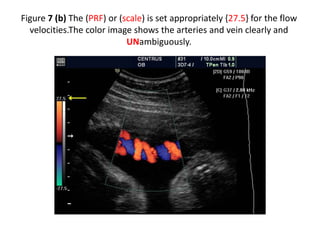

Figure 7 (b) The (PRF) or (scale) is set appropriately {27.5} for the flow

velocities.The color image shows the arteries and vein clearly and

UNambiguously.